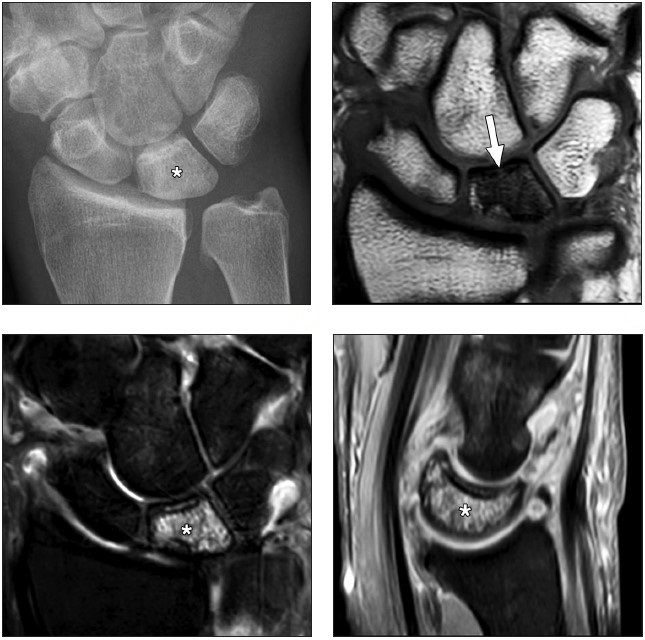

In comparison with acute traumatic injuries to the TFCC, which may affect various components of the complex, chronic ulnar abutment typically causes central degeneration and perforation of the triangular fibrocartilage disk proper, as outlined by the Palmer classification. The spectrum of progressive pathologic changes in ulnar abutment includes degenerative tearing of the TFCC, ulnar-sided chondromalacia, tears of the lunotriquetral ligament, and lunotriquetral instability—and, in advanced stages, osteoarthritis of the distal radioulnar joint and ulnar side of the radiocarpal compartment. The typical areas of cartilage loss and associated reactive marrow changes are localized to the ulnar head, ulnar side of the proximal aspect of the lunate, and radial side of the proximal aspect of the triquetrum (Fig. 1).

Radiography provides the most accurate determination of the ulnar variance and cannot be substituted with other imaging modalities, particularly in the detection of subtle changes that can be determined only by standard radiographic positioning. MRI provides detailed assessment of the TFCC, bone, and articular cartilage. MRI and CT arthrography can be used to determine the integrity of the TFCC and lunotriquetral ligament.

Radiographic staging of Kienböck disease is based on the presence or absence of sclerosis, lunate collapse, carpal instability, and, ultimately, osteoarthritis. MRI allows detection of early radiographically occult disease. On MRI, marrow abnormalities in Kienböck disease, in contradistinction to the ulnar-sided wrist impaction syndromes, affect the lunate more diffusely or predominantly on the radial side without involvement of the triquetrum or reciprocal findings in the ulnar head (Fig. 2).